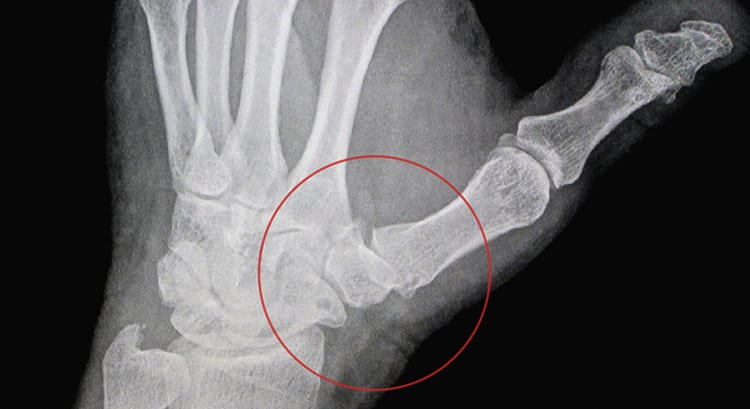

Диагноз выставляется на основании жалоб пациентов, внешнего осмотра, изучения анамнеза. Среди инструментальных исследований наиболее информативна рентгенография. На полученных снимках визуализируются основные признаки артрита:

- сужение суставной щели;

- сформировавшиеся костные наросты — остеофиты;

- разряжение костных структур;

- истончение хрящей;

- наличие участков с кальцинатами.